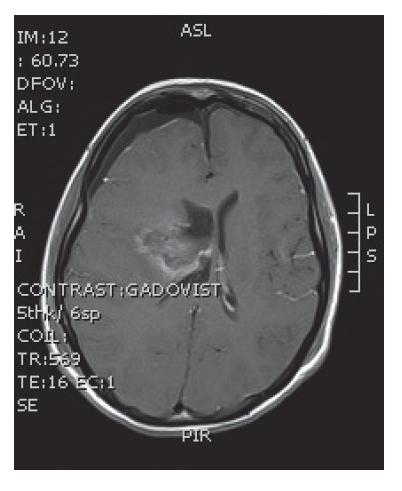

V naší kazuistice prezentujeme 25letou pacientku s negativní onkologickou rodinnou anamnézou, která dosud vážněji nestonala. Udávala asi 3 měsíce progredující bolesti hlavy a krční páteře, zvracení, postupně rozmazané vidění a parestezie horních končetin. Byla provedena magnetická rezonance, na které diagnostikován tumor mozku ve frontálním laloku vpravo, vyplňující frontální roh postranní komory velikosti 6x5 cm, midline shift, mass efekt. Dne 23. 9. 2013 ji byla na neurochirurgické klinice provedena neradikální exstirpace tumoru z parasagitální kraniotomie. Histologicky byl prokázán glioblastom multiforme gr. IV. Od 30. 10. 2013 do 12. 12. 2013 absolvovala konkomitantní radiochemoterapii (radioterapie do CLD 60,0 Gy) s temozolomidem (75 mg/m2 per os D1-42). Od ledna do dubna 2014 pokračovala v chemoterapii temozolomid solo v dávce 150 mg/m2, resp. od 2. cyklu 200 mg/m2 D1-5 ( Temodal tbl, celkem 4x). Na kontrolní MRI mozku ze dne 20. 5. 2014 byla prokázána progrese rezidua. Dne 4. 6. 2014 podstoupila druhou operaci, histologicky verifikován glioblastom multiforme s přechodem v gliosarkom. Snažili jsme se získat informace ze zahraniční literatury s léčbou gliosarkomu, bohužel se jedná o velmi vzácné onemocnění a údajů není mnoho. Nakonec byla zvolena léčba podle protokolu ICE (ifosfamid, carboplatina, etoposid), který je obdobou režimu PEI. Dávky: ifosfamid 1000 mg/m2 D1-3, carboplatina 110 mg/m2 D1 a etoposid 100 mg/m2 D1-3 v pětitýdenním cyklu. Pacientka zahájila 1. sérii od 1.7.2014 s podporou G-CSF (Neulasta s.c.). Léčbu tolerovala dobře, bez akutních či pozdních vedlejších nežádoucích účinků a významné hematologické toxicity. Po 3 cyklech podstoupila kontrolní MRI, kde popsána parciální regrese periferního sycení – rezidua tumoru. Po dalších 3 cyklech chemoterapie provedena restagingová MRI, kde popsána opět mírná regrese rezidua tumoru. Celkový stav pacientky se během léčby postupně zlepšoval, je mobilní, bez psychoorganického syndromu. Byly vysazeny kortikoidy, což vedlo k ústupu cushingoidního syndromu. Bylo rozhodnuto o pokračování v dalších 2 cyklech udržovací chemoterapie, na kontrolní MRI ze 14. 4. 2015 a 7. 7. 2015 popsána stabilizace onemocnění.